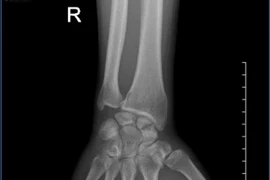

Đau cổ tay kéo dài hình thành khớp giả xương thuyền

Gãy xương thuyền cần được quan tâm đúng mức, tránh bỏ sót thương tổn, có chỉ định can thiệp đúng và hợp lý để tránh bỏ sót, tạo khớp giả, viêm khớp dẫn đến hạn chế vận động cổ tay.